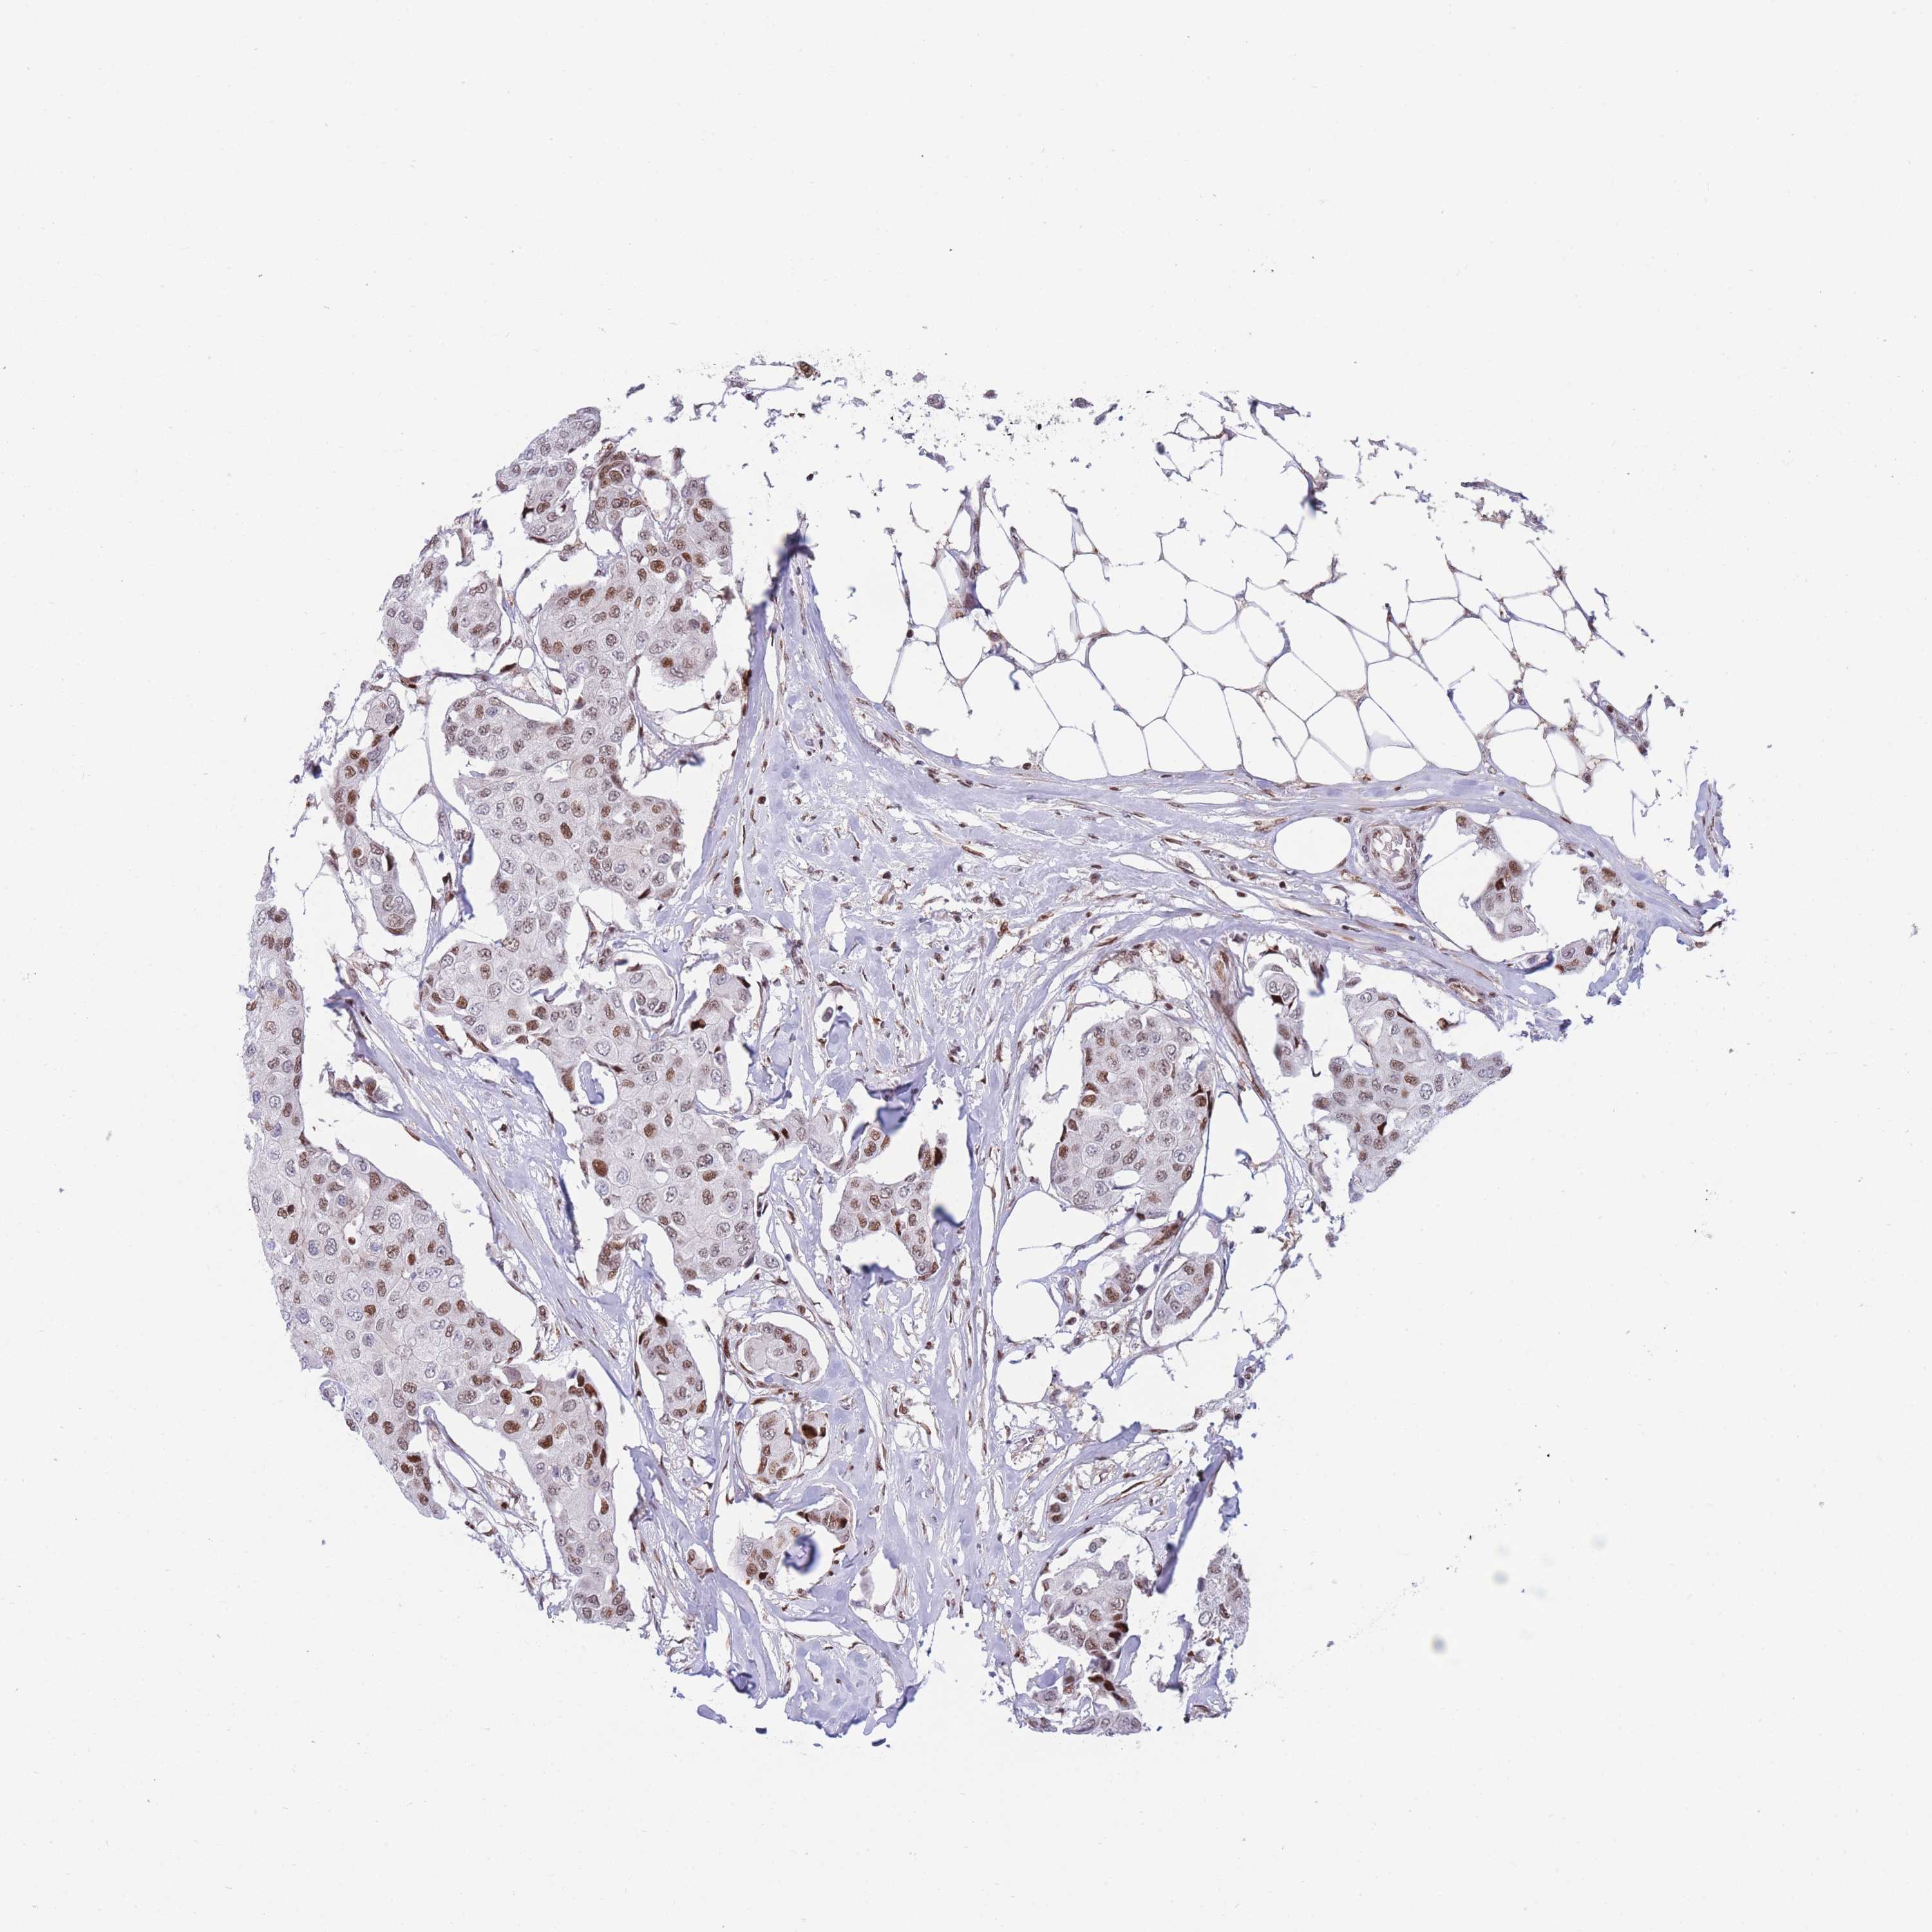

BRCA TCGA BRCA VALIDATION PROTEIN EXPRESSION

ANTIBODIES

AND

VALIDATION